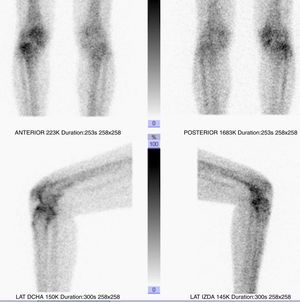

In our case series, the joints treated with radiopharmaceuticals were: 26 (87%) knee with Ytrium-90 (Figs. 2 and 3), 2 (6.7%) ankle with Renium-186 and one (3.3%) shoulder with Erbium-169.